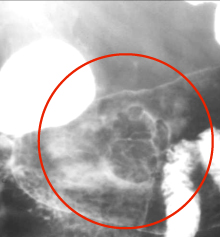

Image en

laculaire eleve intra luminale gastrique a

nultilobulaire ou epassisement de gros plis . S'il y

avait lesion ulceree en association c'est tres

difficile de diagnostic differentielle avec

anenocarcinoma de l'estoma .Image TOGD avec

compressive region antral . |

Meme cas en double de

contrast.TOGD .. |